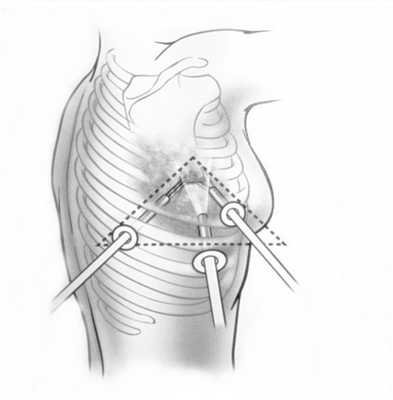

При невозможности получить образец ткани для исследования эндоскопически применяются инвазивные методы: трансторакальная биопсия, медиастиноскопия, видеоторакосокпия. Последние два метода — это серьезные операции, которые проводятся в специализированных медицинских учреждениях.

- Тимомы нуждаются в хирургическом лечении. При высокой степени злокачественности за хирургическим вмешательством следует лучевая терапия. Для удаления опухоли используются различные доступы: как минимально инвазивные и роботические операции, так и открытые «большие» операции (торакотомии и стернотомии).